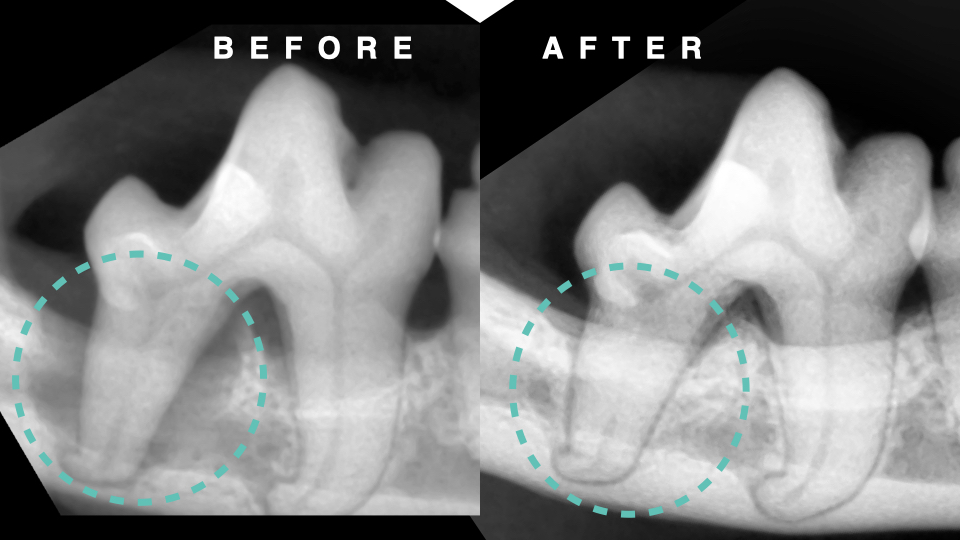

今回の患者さんは、重度の歯周病による下顎第一後臼歯の骨融解を認めたケースです。

レントゲン検査では3壁性の垂直性骨欠損を確認しました。

処置は全身麻酔下で行い、M-MINSTの手技により歯周ポケット底部まで根面清掃を徹底。骨欠損部には自己由来PRFを充填し、歯周組織の再生を促進しました。